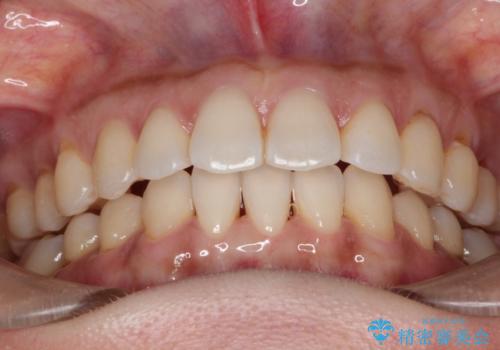

前歯のがたつきと隙間の矯正 インビザラインにて

- 上顎の前歯のがたつきと、下の前歯の隙間を主訴に来院されました。

下の前歯が先天的に欠損していました。

上顎の歯と歯の間をわずかに削りスペースを作り、ガタガタの改善し、下顎の前歯は隙間を閉じる計画としました。

非常に協力的な患者様でしたので、早期に治療が終了することができました。